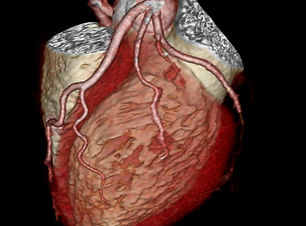

AORTA ABDOMINAL

AORTA TORACICA